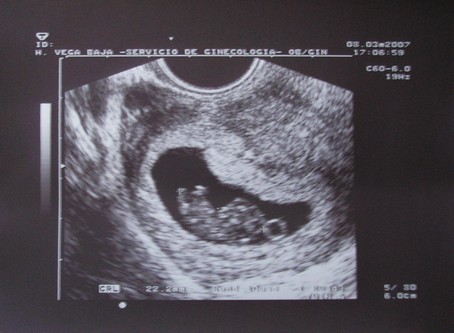

Nagyon jó az UH!!!!!

.... Egyébként B babát én nem igazán látom jól...